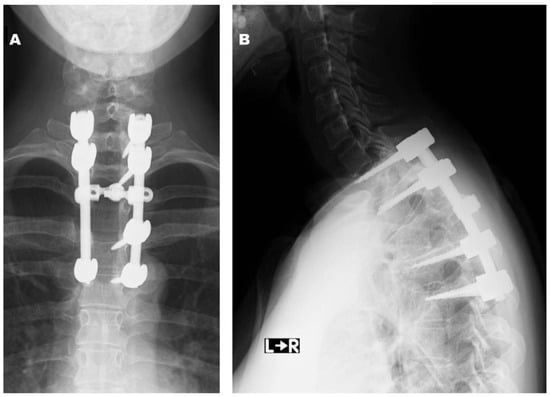

2.1. Case 1

2.2. Case 2